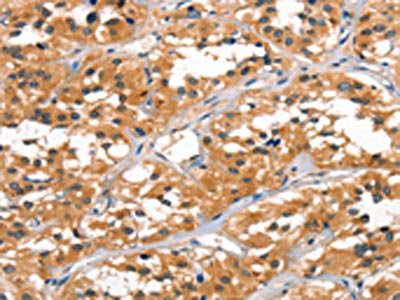

The image on the left is immunohistochemistry of paraffin-embedded Human thyroid cancer tissue using CSB-PA624049(ALOX15 Antibody) at dilution 1/60, on the right is treated with synthetic peptide. (Original magnification: ×200)

The image on the left is immunohistochemistry of paraffin-embedded Human breast cancer tissue using CSB-PA624049(ALOX15 Antibody) at dilution 1/60, on the right is treated with synthetic peptide. (Original magnification: ×200)